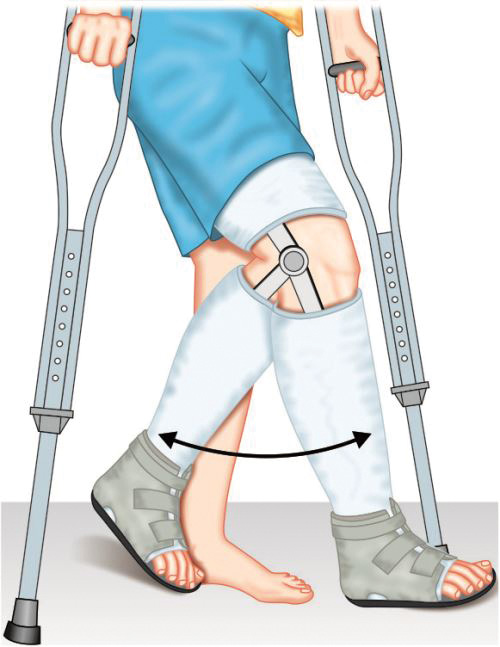

Functional Cast Bracing (Fig. 1.37)

Functional cast bracing concept was popularized in late 1960s by Sarmiento. Initially functional cast bracing was done for tibial fractures but later on for fractured femur and upper limb fractures also. The technique of functional cast bracing consists of applying a splint (called brace) to the fractured limb that while supporting the fracture allows early weight bearing and movement of nearby joints. Early mobilization in this manner encourages the osteogenesis, union and tissue healing. Functional bracing cast is accurately molded around limb in segments which are connected by hinges around joint to allow joint motion while conventional cast bracing immobilizes joints above and below the fracture and restricts their movement.

Functional cast bracing provides less support to fracture than conventional cast so it is applied after 2–3 weeks when fractured ends become sticky and pain and swelling subsides. Early weight bearing is allowed with painless minor movement at fracture site. Thus functional cast bracing prevents joint stiffness, speeds-up rehabilitation and promote osteogenesis and union.